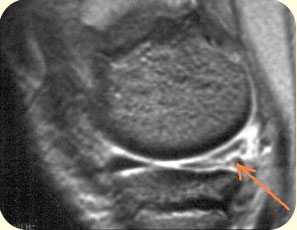

повреждение хряща и субхондрального слоя внутреннего мыщелка бедреной кости

2. ЯМРТ (ядерно-магнитно-резонансная томография) Современный, высокоинформативный, безопасный метод исследования. Лучше всего подходит для определения мягкотканых повреждений: связочного аппарата, повреждений менисков, хряща и др.

разрыв крестообразных связок коленного сустава (изображение слева), разрыв заднего рога внутреннего мениска коленного сустава (изображение справа)

1 - бедренная кость (наружный мыщелок);

2 - большеберцовая кость;

3 - задний рог латерального мениска;

4 - латеральная головка икроножной мышцы;

5 - суставная щель.